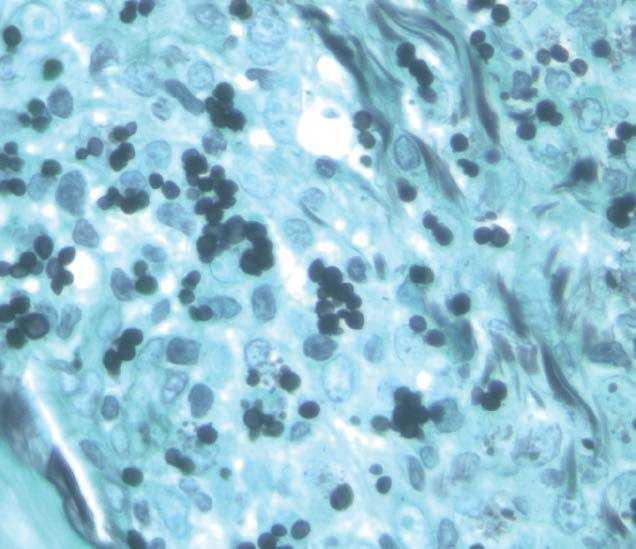

En la exploración física presentaba pápulas eritematovioláceas faciales (fig. 1), fiebre de 39 °C, con hepatoesplenomegalia, siendo el resto de los datos sin interés. En la analítica destacaba pancitopenia, transaminitis, CD4 111/mm3. La intradermorreacción a la tuberculina (PPD) fue negativa. La radiografía de tórax evidenciaba un patrón retículo-nodulillar difuso y bilateral. Los cultivos de esputo, sangre, orina y piel fueron positivos para Histoplasma capsulatum capsulatum. La biopsia cutánea de las pápulas faciales mostró una epidermis sin alteraciones, y un infiltrado inflamatorio linfohistiocitario en dermis media y profunda (fig. 2). Destacaba la presencia de unos elementos basofílicos intrahistiocitarios, reacción del ácido peryódico de Schiff (PAS) y plata metenamina positivos de 2-4 μm de diámetro con un halo periférico alrededor (fig. 3). El paciente fue tratado con anfotericina B endovenosa durante una semana, seguido de itraconazol 400 mg al día, vía oral1, observándose una mejoría clínica y analítica a los 10 días del tratamiento. El reservorio del histoplasma son las aves y los murciélagos. Sus heces contienen hongos.

Figura 3. Elementos de 2-4 μm de diámetro con un halo a su alrededor (plata metenamina, x100).